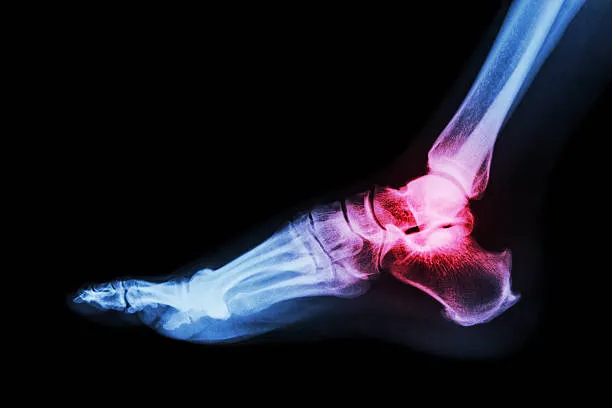

• Intra-articular fractures: fracture extends into the joint surface.

Early arthritis in joints near the fracture.

• X-rays: Initial imaging for fracture location and severity.

• CT Scans / MRI: Detailed mapping of bone fragments, joint involvement, or soft tissue injury.

• Reduces risk of chronic pain and arthritis.